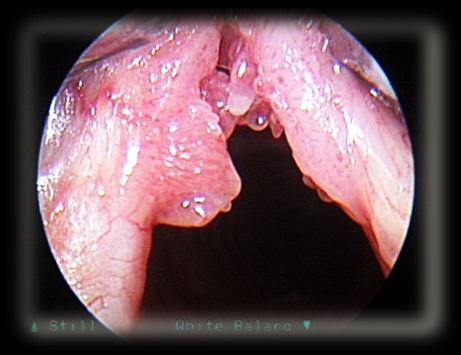

Папиллома